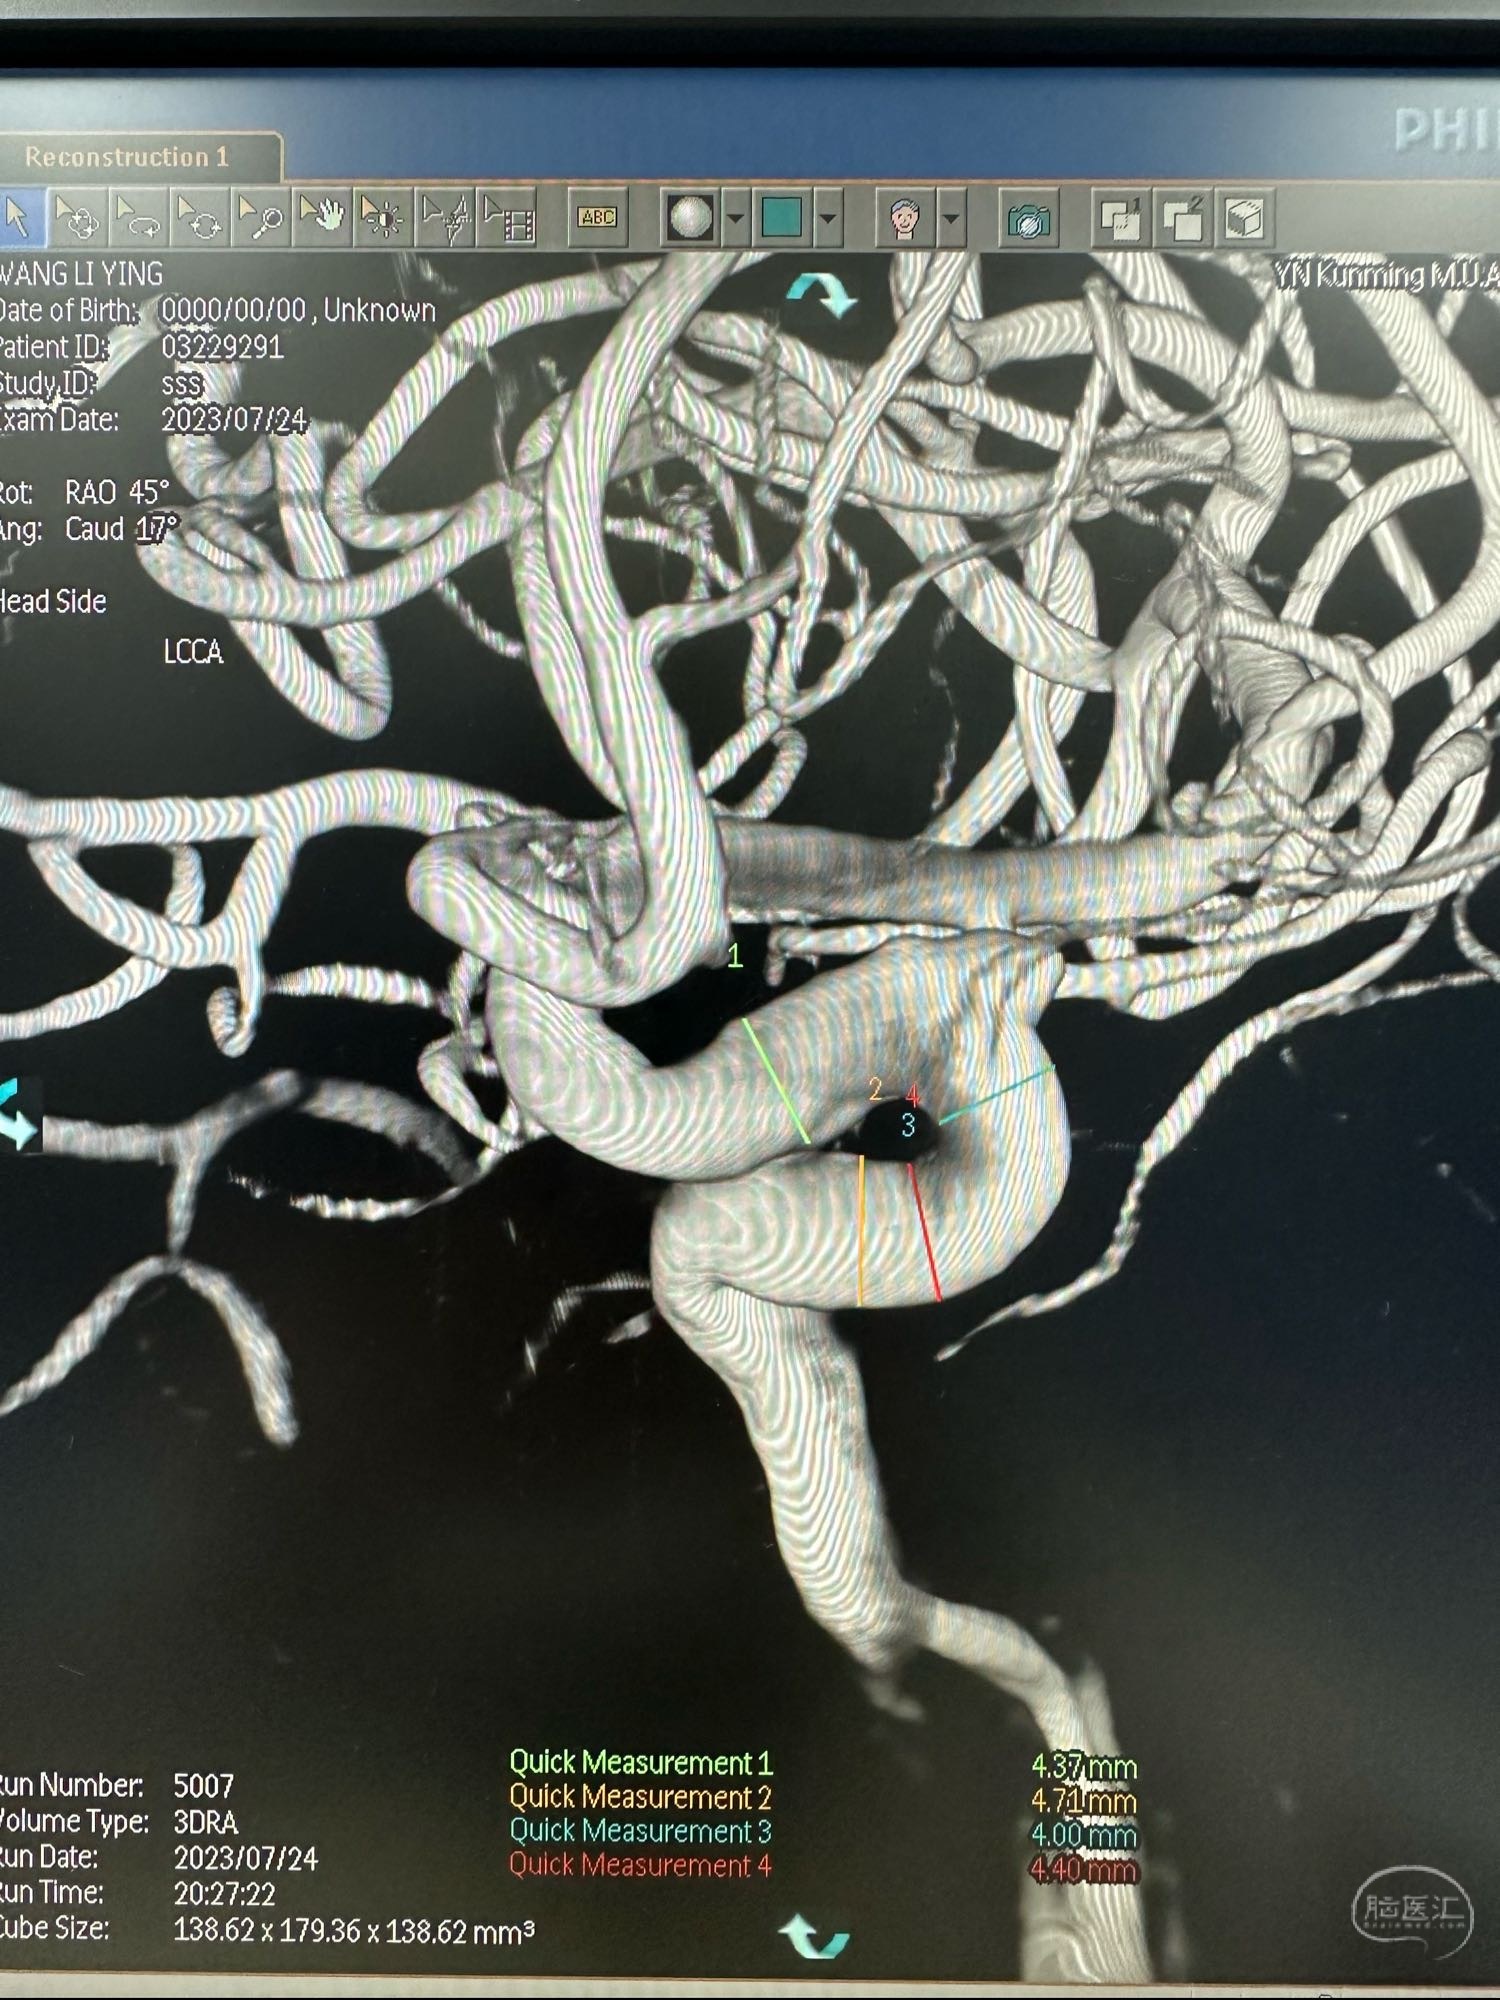

另外一个角度

根据载瘤动脉的直径,选取4.4*20的Lattice的密网支架.进行原位释放.

王LY,女,71岁,左侧眼动脉段动脉瘤,给予Lattice密网支架植入